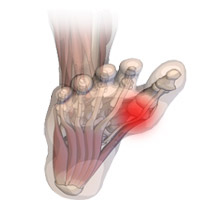

Vbočený palec (Hallux valgus) je velmi častá deformita nohy. může být dědičná, ale často vzniká v pozdějším věku vlivem nošením nevhodného typu obuvi. Deformace vzniká v důsledku ochabnutí vazů a svalů, kdy dojde k poklesu a rozšíření přední příčné klenby (vzniká tzv. rozšlápnutá noha). Následně dochází k přetížení palcové strany nohy, ochabnutí a uvolnění meziprstních svalů, rotaci palce, který mění svou osu. Vlivem tlaku obuvi často vzniká kostěný výrustek, otlaky a kuří oka. Nejlepší prevencí je nošení vhodné obuvi, ortopedických nebo gelových vložek.

Kladívkový prst patří mezi časté deformity prstů dolních končetin, kdy se deformují klouby porušením rovnováhy mezi krátkými a dlouhými svaly nohy. Jsou to jakési skrčeniny prstoů. Postižení se objevuje se stoupajícím věkem a vzniká hlavně na 2. prstu, nicméně může vzniknout na kterýmkoliv prstu kromě palce. Prst se postupně ohýbá, nelze ho narovnat a tlakem obuvi se na vrcholku prvního článku vytvoří otlak, i bolestivé kuří oko.